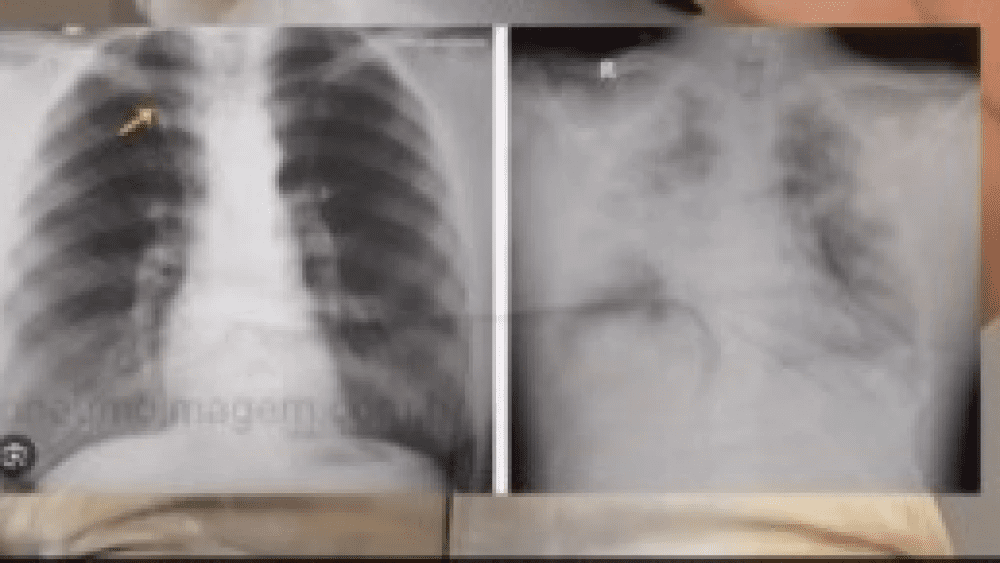

O pulmão do atleta não respondeu ao tratamento como os outros órgãos e a mãe associa que a falta de reação esteja associada ao fato de o filho ser usuário de vape. Na imagem é possível observar o comparativo do pulmão após uso de vape em comparação com o pulmão de um nã-fumante.